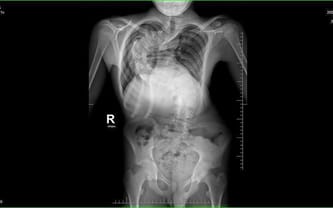

Alan od września ma rozpocząć naukę w szkole ponadpodstawowej. Chciałby żyć tak jak rówieśnicy. Skrzywienie, co widać na zdjęciu RTG, jest ekstremalne, wymaga pilnej korekcji. Trzeba jak najszybciej zebrać fundusze na leczenie operacyjne. Bez Was nie damy sobie sami rady...

Wielu specjalistów, mnóstwo różnych sposobów leczenia, aż wreszcie informacja, że w Polsce nie ma dla niego ratunku. Mamy to napisane na oficjalnym dokumencie medycznym z pieczątką i podpisem. To nie jest żaden wymysł, czy inna fanaberia. Najbliższym miejscem, gdzie mogą pomóc Alanowi, jest czeska klinika w Brnie. Wiąże to się jednak z ogromnym wydatkiem, a nasz wniosek o dofinansowanie z NFZ przepadł. Dlatego musimy prosić Was o pomoc... Jego kręgosłup jest już wygięty o ponad 140 stopni...

Skrzywiony kręgosłup niesie za sobą całe mnóstwo dalszych komplikacji. Oprócz bólu i wstydu z powodu dziwnego wyglądu chory cierpi również przez nacisk na narządy wewnętrzne, takie jak płuca czy serce. Co gorsza, wada cały czas się pogłębia, a Alan przecież cały czas rośnie. Nie wiemy, jak długo jeszcze wytrzyma, a nieprzespane ze strachu noce stały się naszą przykrą codziennością.

Mój syn ma 15 lat, a ja modlę się, by jak najszybciej udało się go uwolnić od koszmaru, jakim jest skolioza. Operacja jest pilnie potrzebna, a w Polsce nie ma ośrodka, który mógłby się podjąć skutecznego i bezpiecznego leczenia operacyjnego. Szansą dla Alana jest operacja przeprowadzona przez profesora Martina Repko w Brnie w Czechach. Koszt takiego zabiegu przekracza nasze możliwości finansowe, a po operacji trzeba wrócić specjalistycznym transportem medycznym.